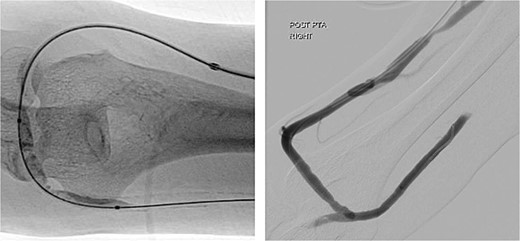

Upon examination 2 days later, the patient’s right hand was significantly colder than his left, with a prolonged capillary refill time of 5 seconds. Pain was alleviated and Doppler signals of his distal arteries were audible only with AVF compression. His digital finger pressure was 36 mmHg, rising to 97 mmHg with fistula compression. A duplex ultrasound revealed patent brachial, ulnar and radial arteries, confirming the diagnosis of DASS (Fig. 3).

Investigations confirming dialysis-associated steal syndrome (DASS).